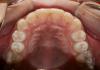

Force Опубликовано 2 ноября, 2009 Поделиться Опубликовано 2 ноября, 2009 (изменено) Как вариант - 6 брекетов изнутри ("невидимки"). Решается только эстетический вопрос в области передних зубов. Недорого (дешевле чем 6 виниров с ваксапом) и зубы не обтачиваются. Сроки - 4-6 мес. Примерно так: Изменено 2 ноября, 2009 пользователем Force Ссылка на комментарий